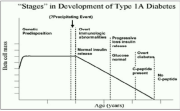

| 04:57, 14 באוגוסט 2023 | התפתחות סוכרת1.png (קובץ) |  |

307 קילו־בייטים | Motyk | 1 | |

| 04:53, 14 באוגוסט 2023 | שלבי סוכרת1.png (קובץ) |  |

102 קילו־בייטים | Motyk | 1 | |